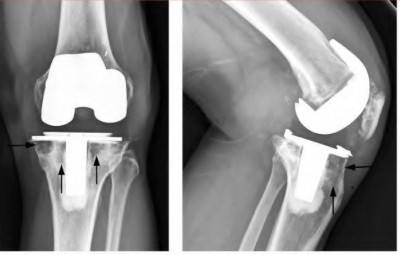

Question 18

During a revision total knee arthroplasty, removal of the tibial component reveals a massive contained metaphyseal defect measuring 3 cm deep, but with an intact cortical rim. According to the Anderson Orthopaedic Research Institute (AORI) classification, what type of defect is this, and what is the preferred method of management?